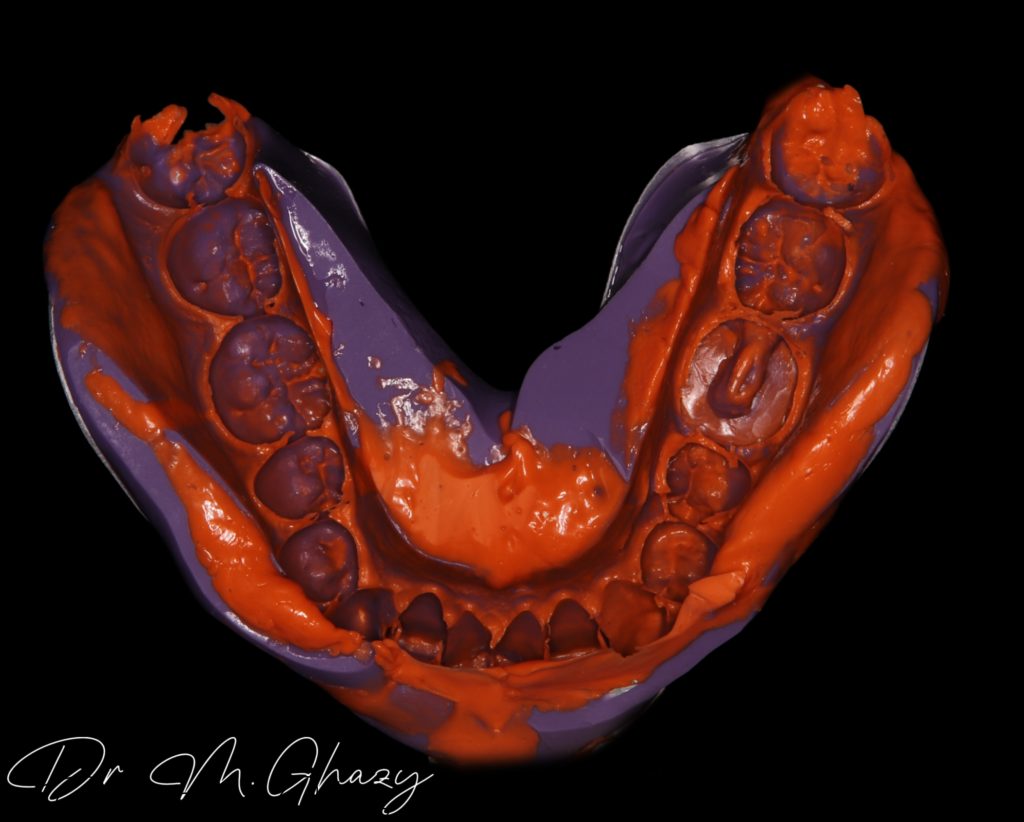

Final impression